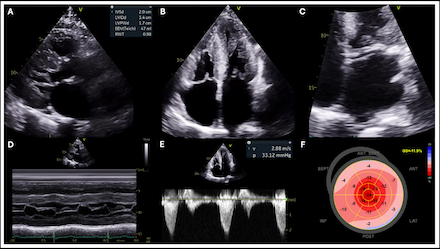

Case: A 65-year-old man with a history of carpal tunnel syndrome, hypertension, and CAA presented with exertional dyspnea. Family history included a brother with hypertrophic cardiomyopathy. Stress testing noted ischemia in the left anterior descending (LAD) and left circumflex (LCX) territories. Invasive angiography and cardiac computed tomography (CT) confirmed an anomalous LAD arising from the right coronary cusp with an interarterial course and a retroaortic LCX arising from the ostium of the right coronary artery without obstructive disease (Figure 1). Echocardiography revealed concentric LV thickening, severe diastolic dysfunction, an apical sparing strain pattern, and dynamic left ventricular outflow tract obstruction (Figure 2). Light-chain amyloidosis was excluded, and cardiac scintigraphy confirmed ATTR-CA (Figure 3). Genetic testing revealed a rare TTR variant of previously uncertain significance (p.Val113Leu), prompting cascade screening.